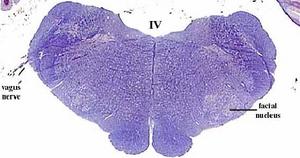

Los núcleos motores del V y VII, y el núcleo ambiguo (origen del IX y X) están formados por una columna de células localizada en la parte ventrolateral del tronco encefálico. Inervan los músculos de la masticación, de la cara, paladar, laringe y faringe.

secciones transversales a diferentes niveles del tronco del encéfalo mostrando la localización de los núcleos neuronales eferentes de los nervios craneales

EFERENTES:

somatoeferentes (SE) : inervan músculos esqueléticos

visceroeferentes(VE): parasimpáticos

correspondencias entre la localización de los núcleos neuronales en diferentes cortes.

esquema de los diferentes núcleos aferentes y eferentes